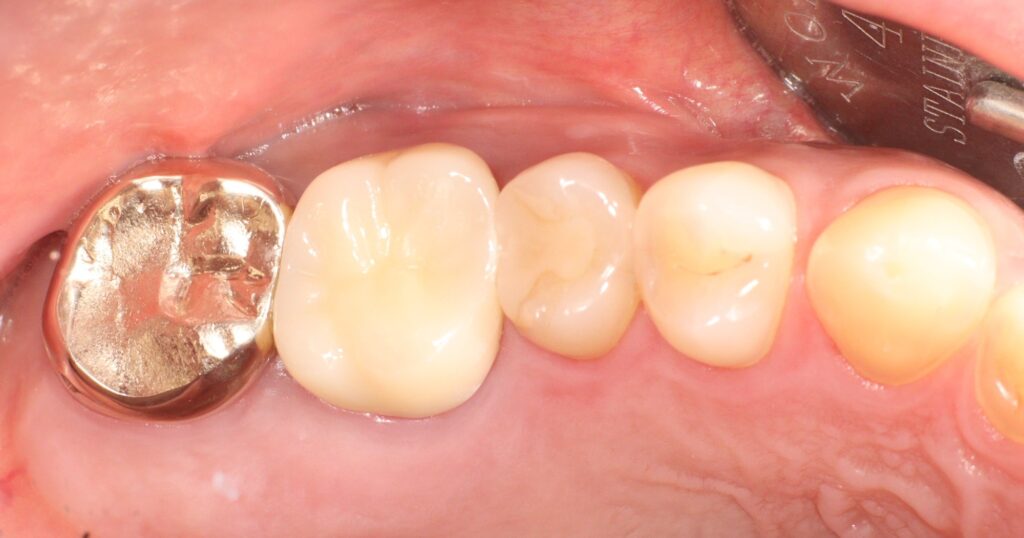

재신경치료가 성공적으로 이루어진 이후에는

재감염을 막기 위해 철저한 관리가 필요한데요.

치료 완료 후에는 빠르게 보철물을 씌워

외부 균의 침입을 방지해야 하며,